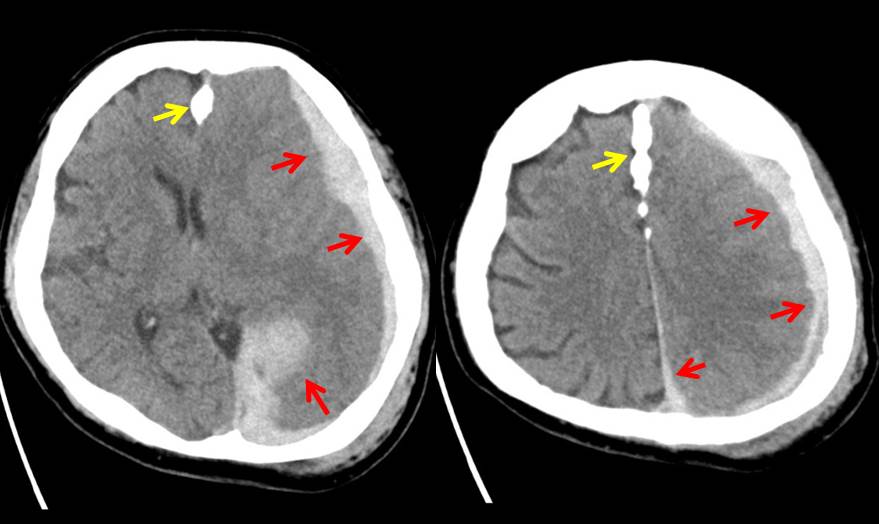

SIMILAR CASE: Acute Subdural Hemorrhage

- Acute subdural haemorrhage (red arrows) is seen at left cerebral hemisphere causing compression to the underlying brain parenchyma, particularly at the left temporal -parietal lobe.

- It extends to left interhemispheric fissure and left tentorium

- It has the maximum thickness of 2.0 cm at left tentorium.

- It is associated with effacement of the adjacent sulci and right lateral ventricle. Poor grey white matter junction differentiation of the left cerebral hemisphere in keeping with cerebral oedema

- There is about 1.1 cm midline shift to the left.

- Prominent temporal horn of the left lateral ventricle noted, in keeping with obstructive hydrocephalus.

- Falx calfication (yellow arrows) as noted on skull radiograph